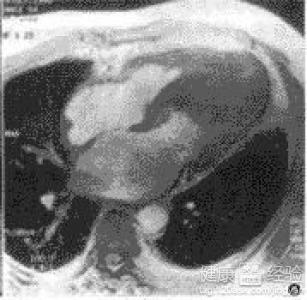

摘要:關(guān)于擴張性心肌病的最新治療,小巷深處的隱藏寶藏正逐漸為人們所發(fā)現(xiàn)。通過先進的醫(yī)療技術(shù)和方法,擴張性心肌病的治療取得了新的進展。這些治療方法旨在改善心臟功能,提高患者生活質(zhì)量。小巷深處的醫(yī)療機構(gòu)或?qū)<铱赡茈[藏著寶貴的治療經(jīng)驗和方法,為尋求最佳治療方案的病患帶來希望。更多詳細信息需要進一步探索和研究。

擴張性心肌病是一種嚴重的心臟疾病,但“心之港灣”為你帶來希望,這里的專家團隊一直在深入研究擴張性心肌病的最新治療方法,并深知每位患者都渴望得到最佳的治療和關(guān)懷,他們努力不懈,為患者帶來生機和新生。

你將了解到最新的藥物治療、心臟康復計劃以及生活方式調(diào)整等方面的知識?!靶闹蹫场边€開展了一系列臨床試驗,為患者提供最新的治療方案,他們的治療方法全面且個性化,因為每個患者的狀況都是獨特的,所以需要因人而異定制治療方案。